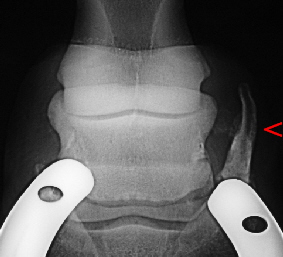

Ansicht eines Strahlbeines von unten bzw. die Skyline Röntgenaufnahme mit Blick auf die Eintrittsöffnungen der Gefäße in das Strahlbein und die Gleitfläche für die tiefe Beugesehne.

Die Kanäle, durch die die Gefäße in das Strahlbein ziehen, sind auf den Röntgenbildern als so genannte "Strahlbeinkanäle" (Canales sesamoidales) zu sehen und spielen bei der Diagnostik einer Hufrollenerkrankung (Podotrochlose) traditionell eine völlig überzogene Rolle.

Die alleinige röntgenologische Nachweisbarkeit von Gefäßkanälen ist nach heutigem Wissensstand kein hinlänglich sicherer Hinweis auf Erkrankung oder Schmerzhaftigkeit, sofern die Gefäßkanäle nicht eindeutig krankhaft verändert sind.

Links im Röntgenbild nicht krankhafte Gefäßkanäle, rechts krankhafte Gefäßkanäle.

Im rechten Bild ein Beispiel für ein Strahlbein mit hochgradig veränderten Gefäßkanälen. Veränderungen in diesem Ausmaß sind natürlich eindeutig krankhaft. Die innere Zerstörung des Strahlbeins geht einher mit dem Einbruch der Gleitfläche und Verklebungen mit der tiefen Beugesehne. Solch hochgradige Veränderungen sind therapeutisch nicht beeinflussbar und daher nach wie vor unheilbar. Pferde mit diesen Veränderungen sind chronisch lahm und müssen aus ethischen Gründen euthanasiert werden.